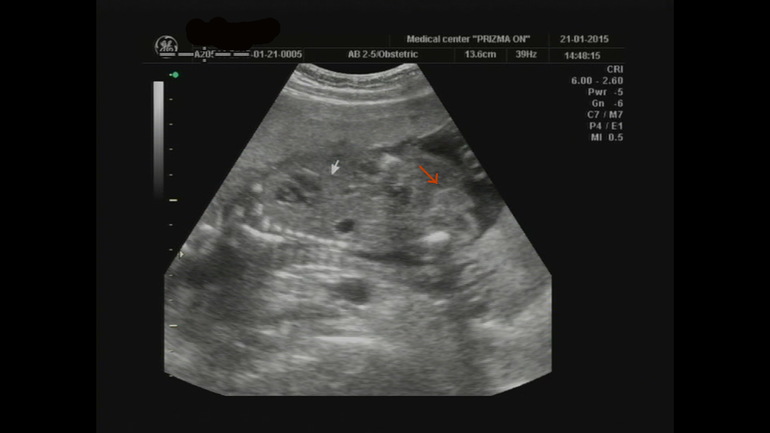

УЗИ, КТГ, доплерДевочки,у кого родился мальчик, такое было узи? это не трехмерный снимок, на самом трехмерном как то яички хорошо видно, но пистончика не видно, так фото вышло и видео, но врач уверяет ,что несомнительно мальчик, а у вас такое фото мальчиков_?

Ну так хорошо видно яички!!!!!брльше по яиичкам смотрят, чем по писюну :)

У нас тоже такая примерно фотка есть, там мошонка и пенис тоже видно, просто ракурс такой))).